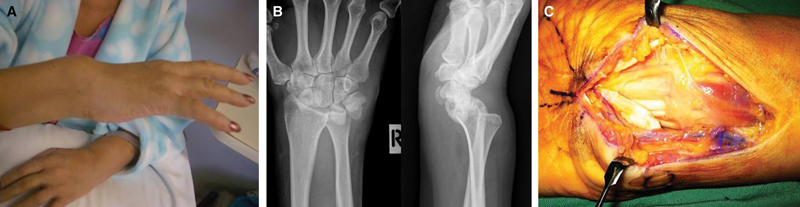

Nineteen days after admission, the patient showed signs of bilateral median nerve compression. The right wrist appeared clinically deformed, with palpable synovitis (Box 2A ). Imaging showed disruption of the right wrist and carpus to a degree usually associated with high-energy trauma (in the absence of any history of trauma), with dislocation of the distal radioulnar joint (DRUJ), and wide diastasis of the scapholunate interval (Box 2B). The left wrist and carpus showed lesser disruption.

The following day, the patient underwent aspiration of the left knee effusion, and bilateral carpal tunnel decompression and flexor synovectomy. Extensive synovitis was observed around the flexor tendons of both wrists (Box 2C), with rupture of the right lunotriquetral ligament. The right DRUJ was reduced and held in a supination splint, avoiding the insertion of metalware until infection had been excluded.